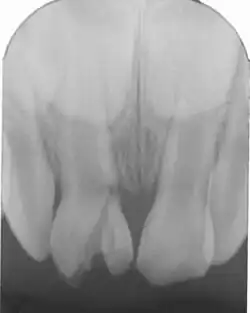

Kronenfraktur mit teilweise subgingivalem Frakturspalt

Ausschlaggebend für die Unterteilung und Therapie der Wurzelfrakturen ist deren Lage im oberen, mittleren oder unteren Wurzeldrittel.

Selbst bei Frakturen im oberen Wurzeldrittel kann die Zahnkrone oft erhalten werden und muss nicht extrahiert werden. Liegt die Fraktur subkrestal wird das frakturierte Fragment über einen lange Zeitraum geschient und kann wieder hohe Stabilität erlangen. Liegt die Fraktur suprakrestal, besteht eine hohe Wahrscheinlichkeit zum Ausbleiben einer Heilung. In diesen Fälle sollte das koronale Fragment entfernt und die verbleibende Wurzel versorgt werden. Zur Erhaltung des Zahnes kann eine Wurzelkanalbehandlung und danach eine prothetische Versorgung mit einer Zahnkrone erforderlich sein. Die Verankerung der Krone mittels Wurzelstift ist häufig sinnvoll (Stiftkrone). Ein Aufbau der klinischen Krone mit Komposit (Kunststofffüllung) ist nur möglich, wenn die Fraktur unmittelbar in Höhe des Zahnhalses erfolgt ist. Bei Frakturen im mittleren und unteren Wurzeldrittel ist eine Erhaltung des Zahnes meistens möglich – der Zahn sollte nicht extrahiert, sondern geschient werden. Mit einer Ausheilung der Fraktur in der Wurzel ist in den meisten Fällen zu rechnen.

Bei subgingivaler Lage der Wurzelfraktur in Höhe des Zahnhalses ist keine ausreichende Trockenlegung für eine Kompositfüllung möglich. Die frakturierte Zahnwurzel kann eventuell verlängert werden: